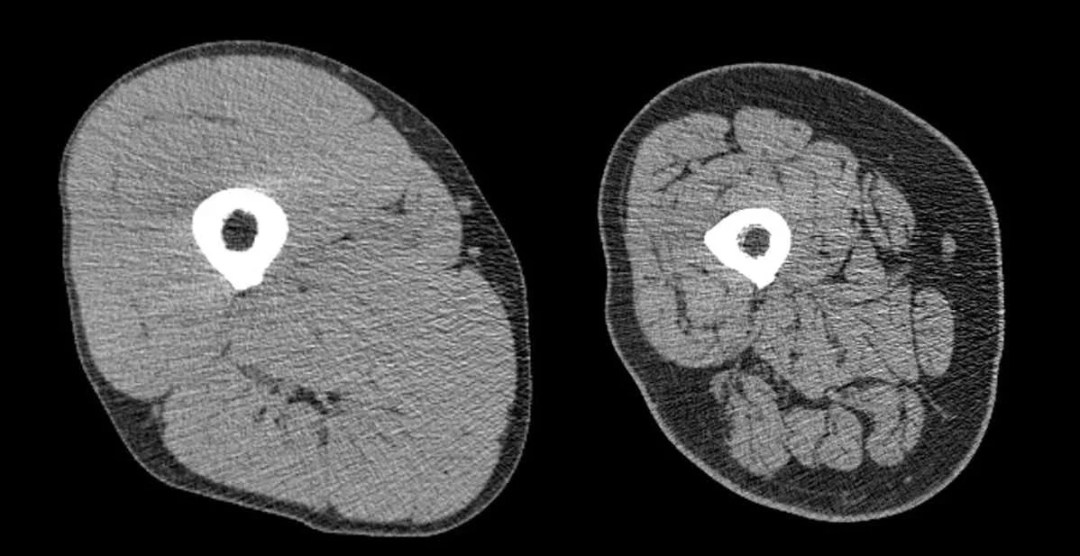

La sarcopenia es la pérdida progresiva y generalizada de masa muscular y fuerza, que puede llevar a discapacidad física, menor calidad de vida e incluso aumento del riesgo de caídas y fracturas1. Inicia desde la cuarta década de vida y se acelera a partir de los 60 años.

Se estima que los adultos pierden entre 3% y 8% de su masa muscular cada década después de los 30 años2. La buena noticia es que no es inevitable en su forma más grave: la actividad física y una alimentación adecuada son claves.